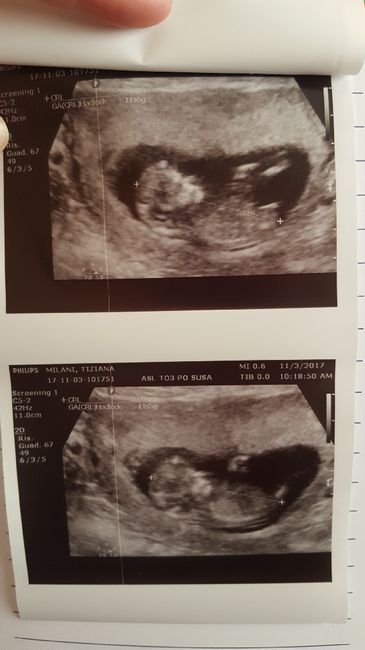

Qst è la mia piccola a 13+0 in occasione della traslucenza andata benissimo, aspetto i risultati del duo test, il dottore già una settimana prima ci aveva detto che probabilmente poteva essere un 🎀 e lo ha confermato lunedì, sono 6,5 cm di amore 💕😍

Future mamme maggio-giugno/2018 1